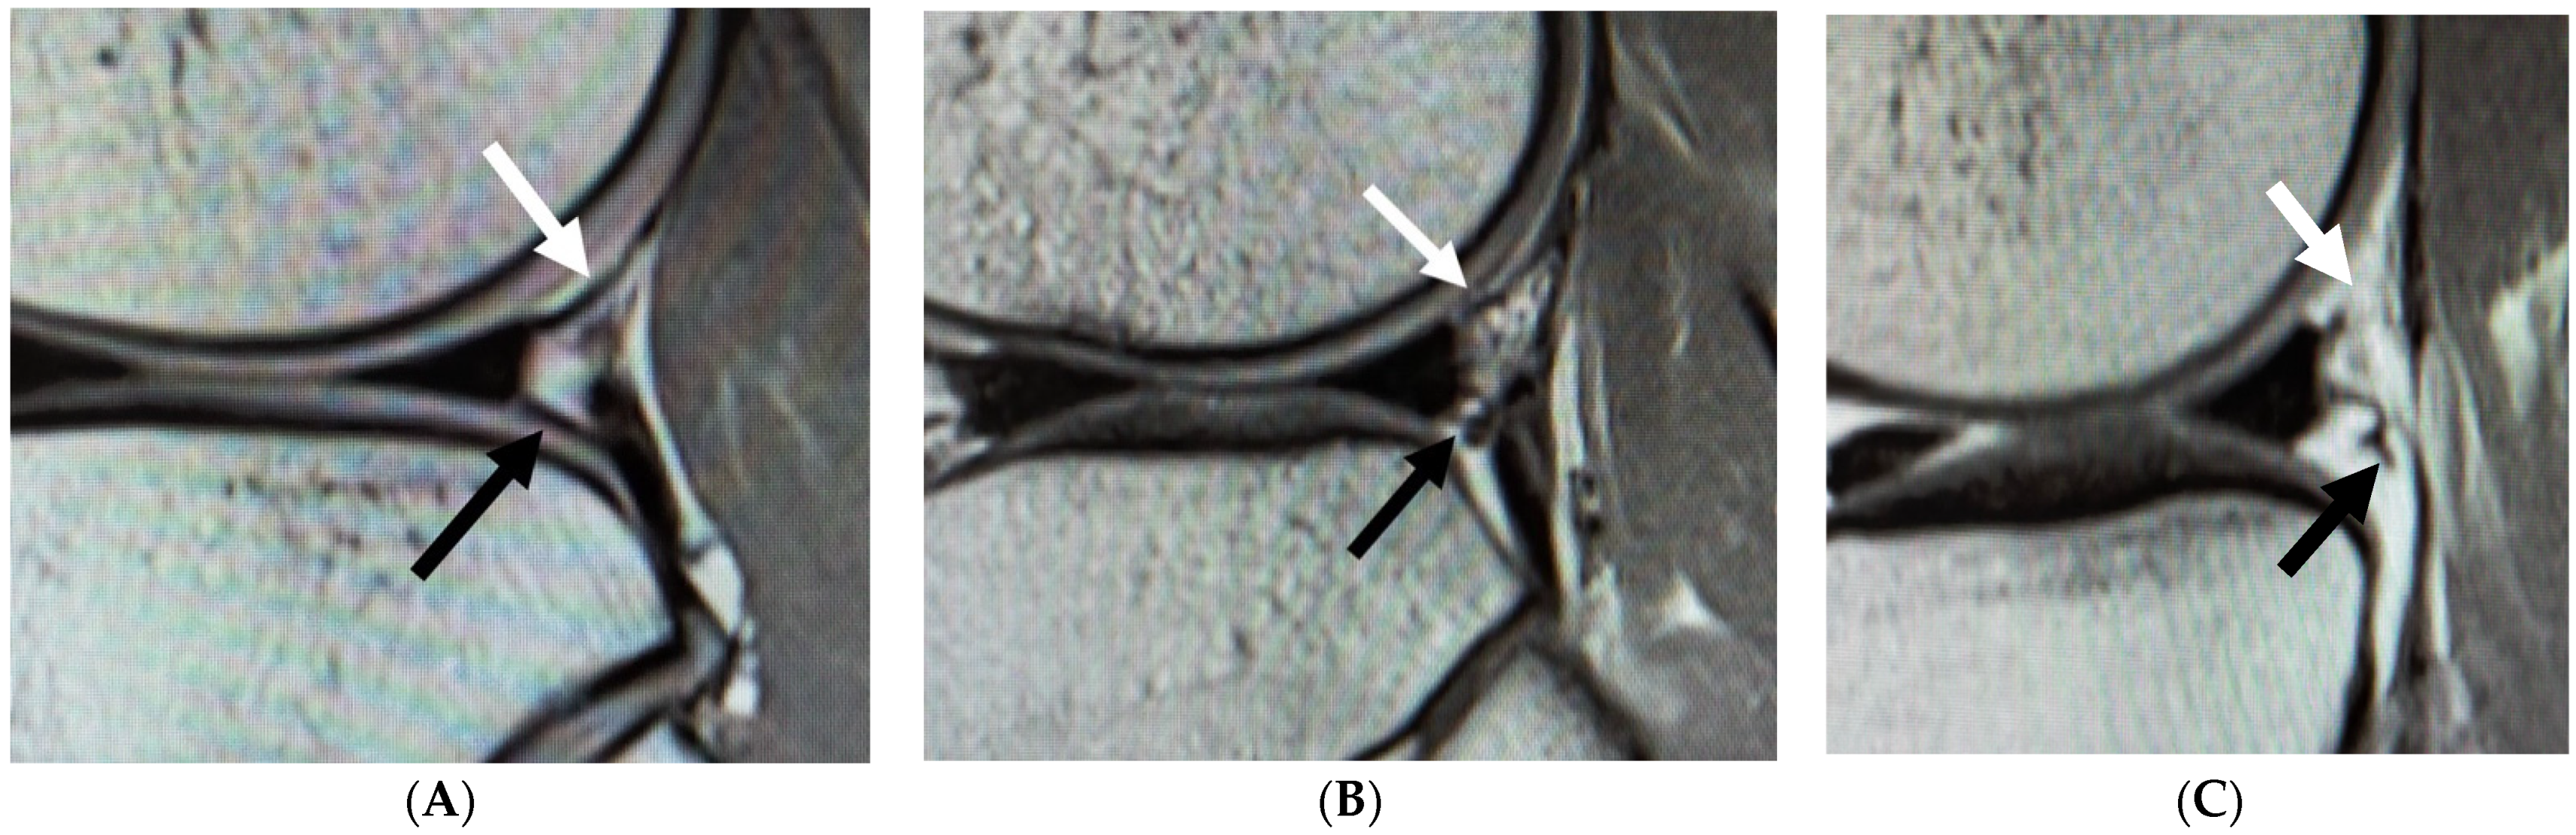

2.2. MRI Measurement

- Suganuma, J.; Mochizuki, R.; Inoue, Y.; Yamabe, E.; Ueda, Y.; Kanauchi, T. Magnetic resonance imaging and arthroscopic findings of the popliteomeniscal fascicles with and without recurrent subluxation of the lateral meniscus. Arthroscopy 2012, 28, 507–516. [Google Scholar] [CrossRef] [PubMed]

- Shin, H.K.; Lee, H.S.; Lee, Y.K.; Bae, K.C.; Cho, C.H.; Lee, K.J. Popliteomeniscal fascicle tear: Diagnosis and operative technique. Arthrosc. Tech. 2012, 1, e101–e106. [Google Scholar] [CrossRef]

- Zheng, J.; Xiao, Q.; Wu, Q.; Deng, H.; Zhai, W.; Lin, D. Tears of the Popliteomeniscal Fascicles of the Lateral Meniscus: An Arthroscopic Classification. Cartilage 2020, 2020, 1947603520980156. [Google Scholar] [CrossRef]

- Sakai, H.; Sasho, T.; Wada, Y.; Sano, S.; Iwasaki, J.; Morita, F.; Moriya, H. MRI of the popliteomeniscal fasciculi. AJR Am. J. Roentgenol. 2006, 186, 460–466. [Google Scholar] [CrossRef] [PubMed]